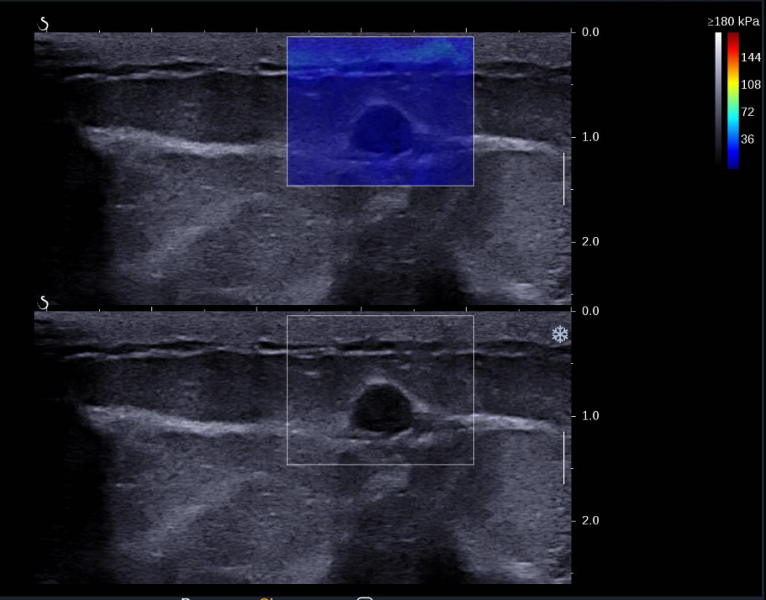

图 3 右乳低回声结节弹性成像显示结节质地较软

右乳可见一个低回声结节,大小约 7×4mm ,形态呈椭圆形,边缘光整,平行方位,内部回声分布尚均匀。

右乳低回声结节, BI-RADS 3 类,建议定期随访,右侧腋窝低回声结节,神经鞘瘤可能,建议粗针穿刺活检(图 1-3 )。